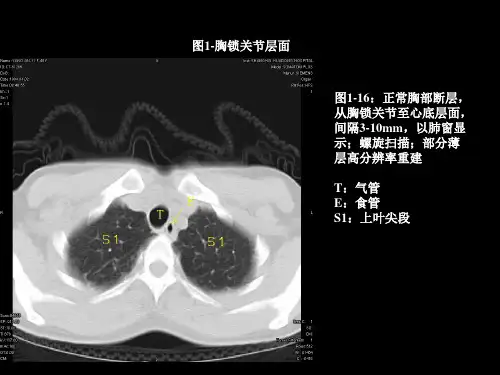

什么是胸部CT 检查胸部CT 检查主要用于全面观察胸腔内部及胸壁结构,提供肺部、心脏、食道、气管、纵隔和其他相关结构的详细信息。

通过使用X 射线和计算机技术,胸部CT 能够生成高分辨率的横截面图像,结合患者的症状、病史等,方便医生判断肺部是否存在肿块、感染性病变或其他异常,以及病变的良恶性、病变范围等。

同时,CT 扫描还能提供心脏及胸腔大血管的清晰图像,有助于评估心脏及大血管的健康状况。